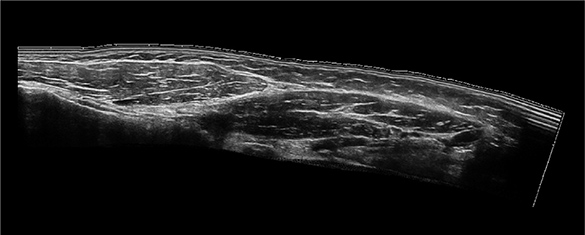

Panoramic Imaging

Allows continuous scanning across large anatomical areas to create a single panoramic image, enabling visualization beyond a single frame and supporting vascular and musculoskeletal evaluation.